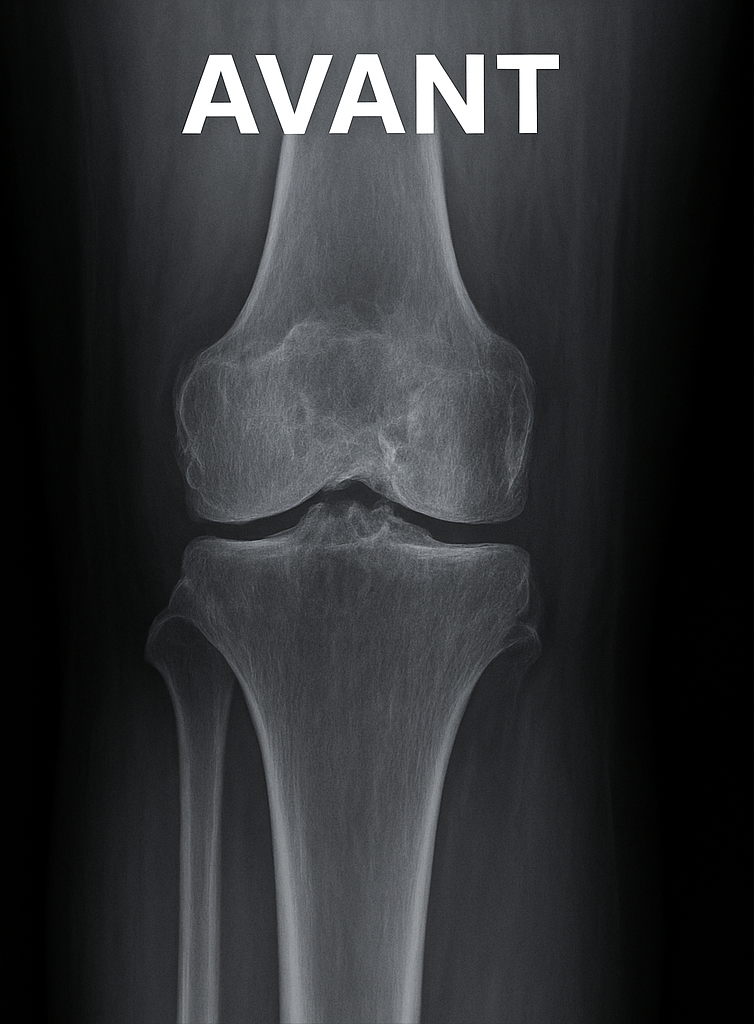

Prothèse du genou